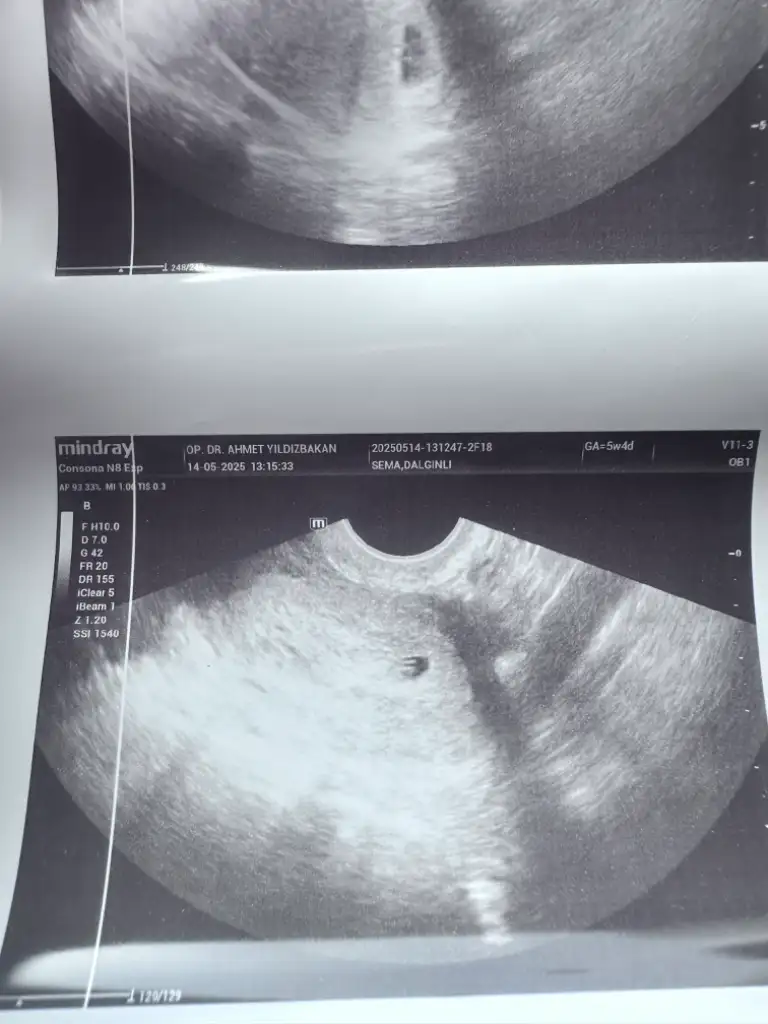

Kızlar keseme bakar mısınız normal mi 5+2 bugün doktor dedi bebek var içinde 10 gün sonra kalp atışına çağirdi